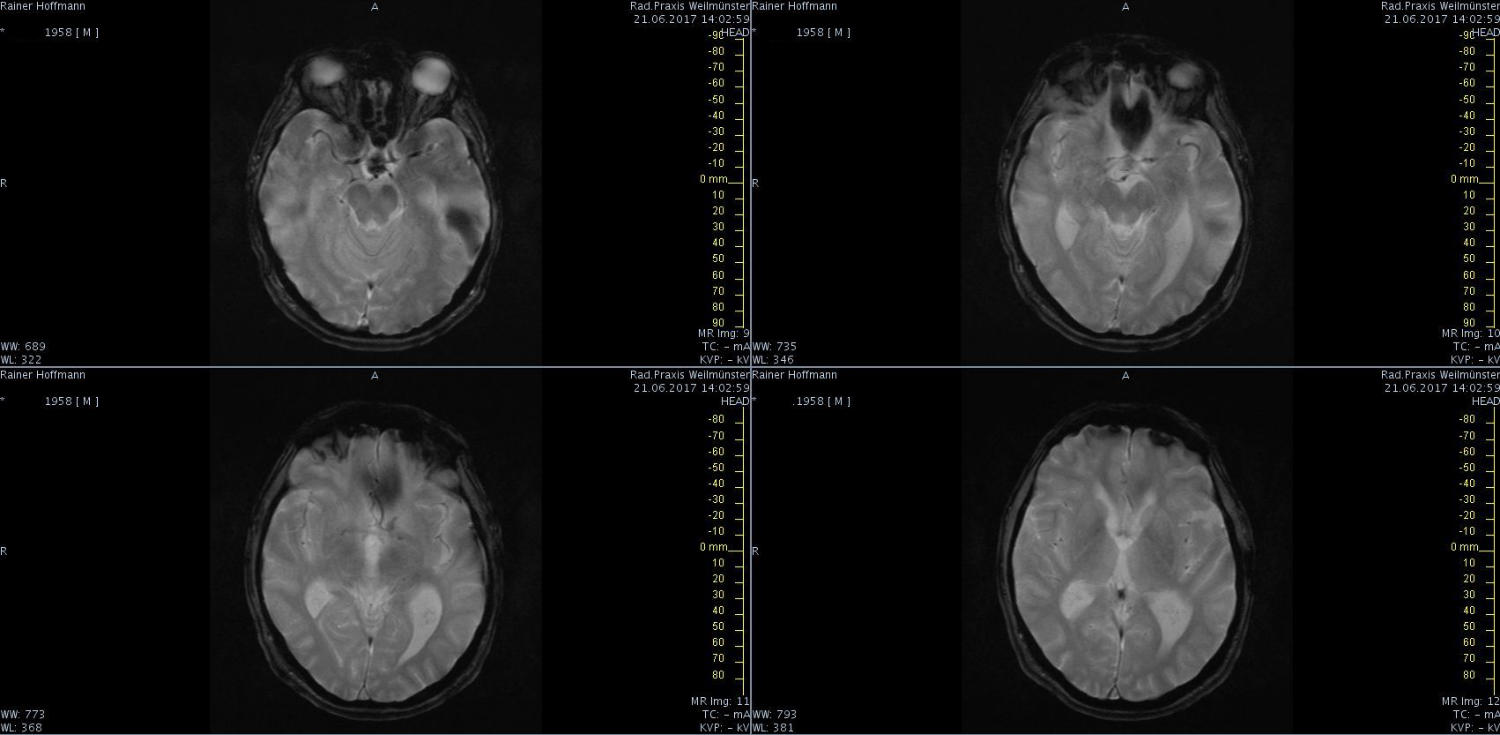

Das ist ja ganz toll, dass Ihr die Seite so schnell gefunden habt. Ich zeige euch jetzt ein ganz, ganz anderes Paßfoto von mir. Es könnte Ähnlichkeiten zu anderen lebenden oder bereits verstorbenen Personen geben. Wenn Ihr das erste Bild oben links anklickt wird es ver- größert dargestellt. Dann kann man mit den Pfeiltasten am unteren Bild- rand durch meinen Kopf blättern. Es gibt nicht viel zu sehen. Vielen Dank an Martina für Ihre Hilfe.

MRT